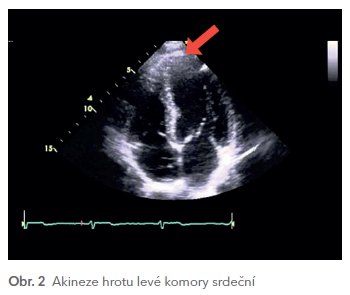

Měli jsme tedy před sebou velmi mladou pacientku, asymptomatickou a zcela nerizikovou z hlediska kardiovaskulárních onemocnění, která měla ovšem jasně patologické EKG – a podle všeho nově. Proto byl doplněn náběr troponinu I, který byl v normě (hs‑TnI 2,8 ng/l), a echokardiografické vyšetření. To prokázalo akinezi hrotu levé komory srdeční a hraniční systolickou funkci (EF 53 %), tedy nález v souladu s negativitami T vln na křivce EKG (obr. 2).